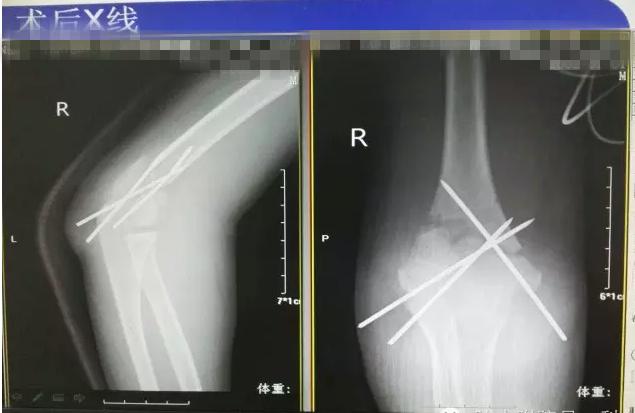

病案二:患儿谭XX,男,14岁,摔伤后右肘关节疼痛伴活动受限5小时入院。

肱骨髁上骨折闭合复位手术记录,小儿肱骨髁上骨折手术恢复的概率 诊断:Gartland III型骨折

肱骨髁上骨折闭合复位手术记录,小儿肱骨髁上骨折手术恢复的概率

术后长臂石膏维持屈肘中立位固定